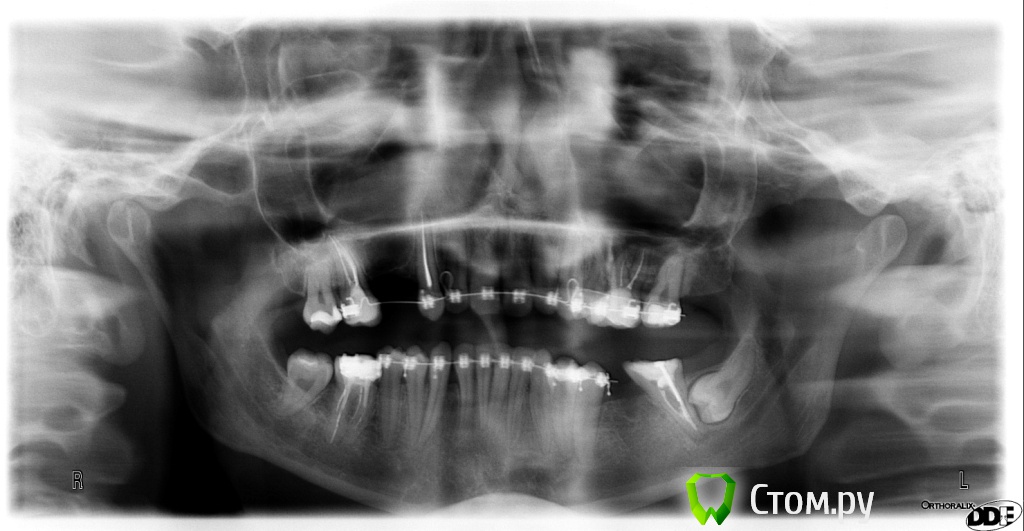

pupsenok Опубликовано 15 ноября, 2013 Поделиться Опубликовано 15 ноября, 2013 Добрый вечер,уважаемые врачи!2,5 года прохожу ортодонтическое лечение на брекетах.Следующий этап - протезирование.Хотела бы услышать Ваше мнение по этому вопросу, в частности по протезированию верхней челюсти импланты либо мост. Ссылка на комментарий